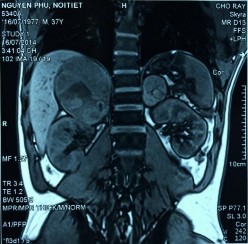

Phim MRI bướu tuyến thượng thận 2 bên

Bệnh phẩm bướu sắc bào tủy TTT bên trái

Phim MRI sau phẫu thuật cắt bướu TTT bên trái

[Nguyễn P., 37 tuổi, SNV: 214061952]